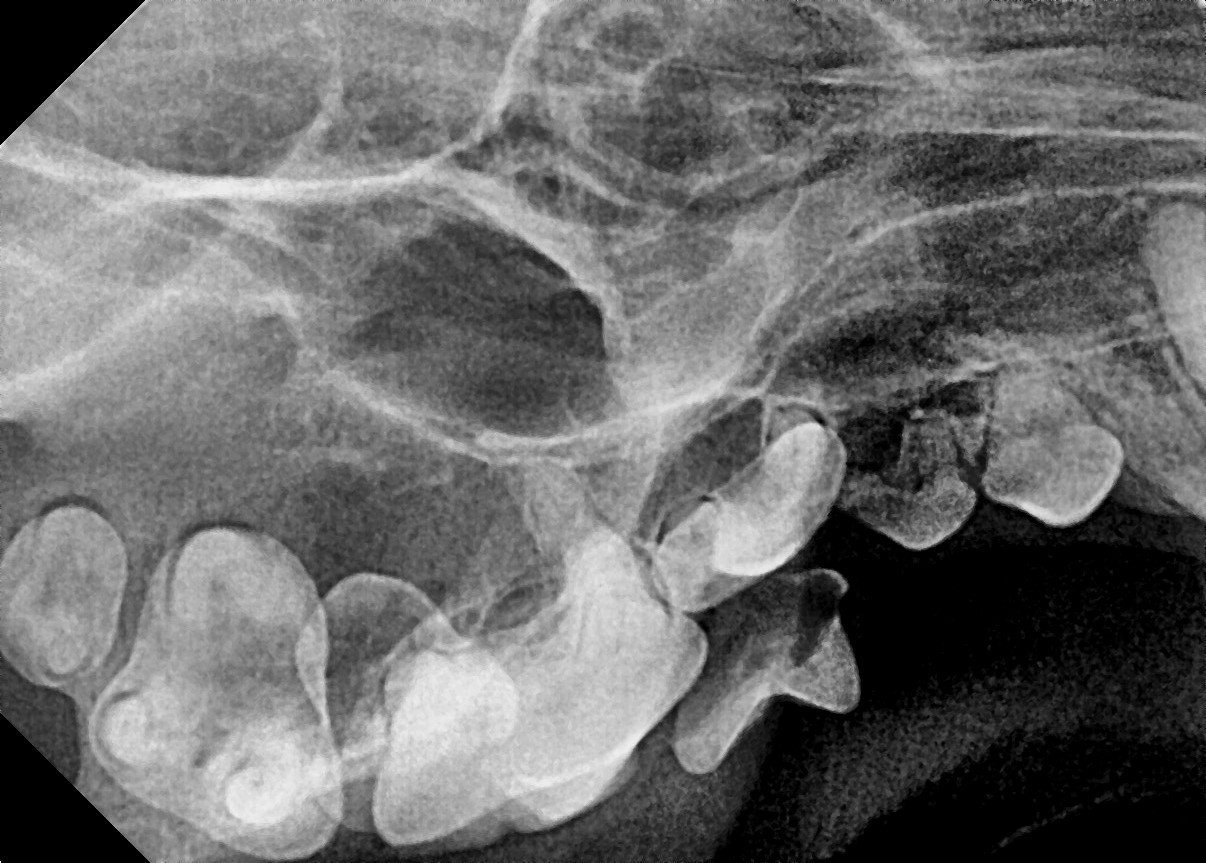

다음은 본원에 내원하여 잔존 유치를 발치한 사례입니다.

이번 사례는 송곳니 유치가 제때 빠지지 않았을 때 생길 수 있는 문제와 그 해결방법에 대하여 말씀드리고자 합니다.

강아지 치아를 관찰해 보면 덧니가 쌍으로 있는 경우가 있습니다.

흔히 덧니라고 알고 있는 치아가 탈락되지 않은 잔존 유치인 경우가 많습니다.

잔존 유치가 탈락되지 않아 영구치가 치아 사이에 같혀 있음 위 사진은 유치가 제때 탈락되지 않아 영구치가 세 번째 앞니 아래에 갇혀 있는 것을 보여줍니다.

세 번째 앞니도 송곳니 간섭으로 인해 정상위치 보다 위쪽으로 벗어나 있는 것(deviation)을 확인할 수 있습니다.

잔존 유치를 제거해 주었더니 별다른 교정 장치를 사용하지 않았음에도 2주 후 제위치로 이동하고 있는 송곳니를 확인할 수 있습니다.